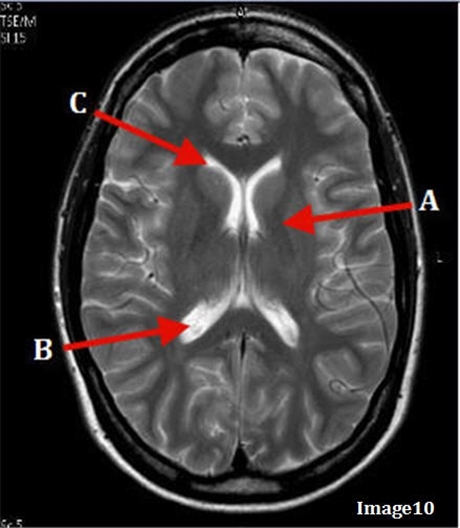

Image weighting and axis

T2 Axial

A

Basal Ganglia

B

Posterior horn lateral ventricle